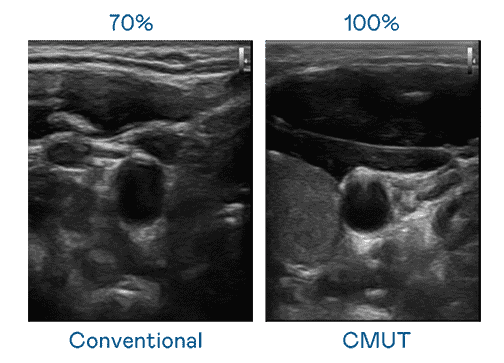

CMUT 技术是一种用电容式微机电元件来产生超音波讯号的技术。。与传统 PZT 压电式技术相比,,,,CMUT 频宽增加 30%,,,,更宽频的超音波讯号让影像解析度大幅提升,,是实现高影像品质医疗超音波扫描、、促进精准医疗发展的关键技术。。。。

大频宽带来超清晰影像

超音波影像的解析度高低,,,,首先取决于探头能发出的讯号频宽。。尊龙z6 CMUT 可提供高清晰的超音波讯号,,,提供高频宽、、、、高灵敏度、、影像纹理细节更高的超音波影像,,,协助医护人员缩短影像判读时间及利用精准的医疗影像进行诊断。。。。